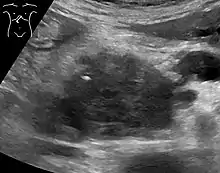

Axial CT image with IV contrast and added color. Cross lines towards top left surround a macrocystic adenocarcinoma of the pancreatic head.

Abdominal ultrasonography of pancreatic cancer (presumably adenocarcinoma), with a dilated pancreatic duct to the right.

Medical imaging techniques, such as computed tomography (CT scan) and endoscopic ultrasound (EUS) are used both to confirm the diagnosis and to help decide whether the tumor can be surgically removed (its "resectability").[12] On contrast CT scan, pancreatic cancer typically shows a gradually increasing radiocontrast uptake, rather than a fast washout as seen in a normal pancreas or a delayed washout as seen in chronic pancreatitis.[50] Magnetic resonance imaging and positron emission tomography may also be used,[11] and magnetic resonance cholangiopancreatography may be useful in some cases.[30] Abdominal ultrasound is less sensitive and will miss small tumors, but can identify cancers that have spread to the liver and build-up of fluid in the peritoneal cavity (ascites).[12] It may be used for a quick and cheap first examination before other techniques.[51]